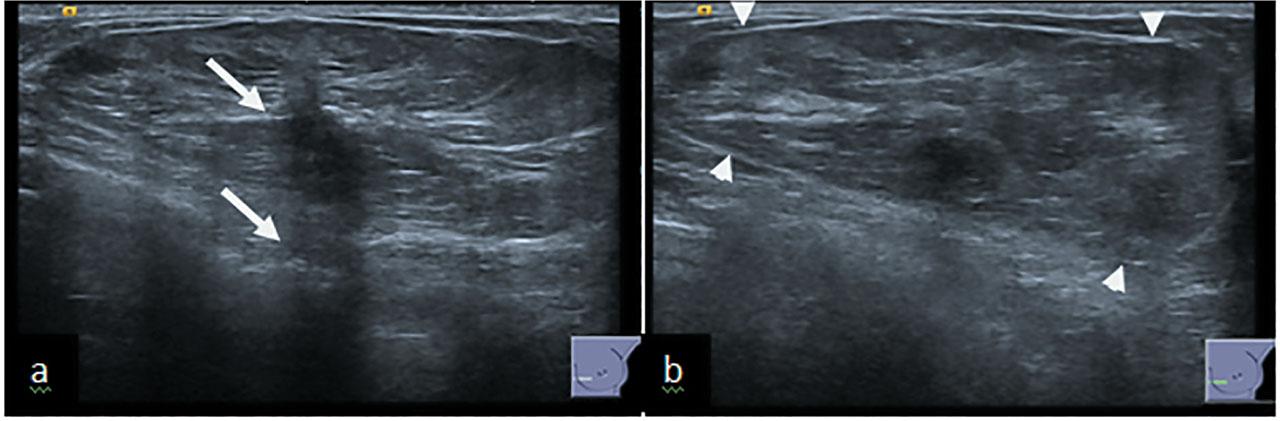

51-year-old female presented to a symptomatic breast clinic with a long standing lump in her left breast. Clinical examination of left breast showed a soft mobile mass. Examination of axilla was normal. Full field digital mammography (FFDM) and ultrasound (US) of left breast was performed. Mammography showed well encapsulated 70mm heterogenous mass consistent with a breast hamartoma in the lower inner left breast with lucent and dense areas mimicking breast tissue. The center of the hamartoma showed an area of distortion with associated calcification (Figure 1a&b). On US there was an oval, well defined heterogenous mass with posterior acoustic shadowing area (Figure 2a&b). Imaging raised suspicion of underlying malignancy within the hamartoma, and a 14 G ultrasound guided core biopsy was performed through the distortion and biopsy marker placed.

(a) US of hamartoma showing a central small hypoechoic area with associated acoustic shadowing (arrow). (b) The thin echogenic pseudocapsule can also be appreciated (arrowheads).